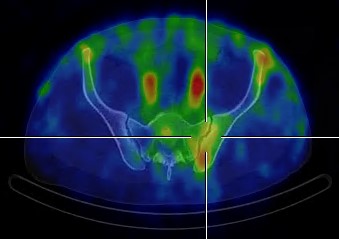

37letý pacient indikován ortopedem pro scintigraficky potvrzenou výraznou synovialitidu levého SI skloubení

(obr.1, 2). Klinicky výrazná klidová i zátěžová bolest, omezení pohybu - značné zhoršení v posledních měsících.

/ Obr.1.: SPECT/CT v axiálním řezu - zvýšený krevní pool v oblasti levého SI skloubení.

/ Obr.2.: SPECT/CT v koronárním řezu - zvýšený krevní pool v oblasti levého SI skloubení.